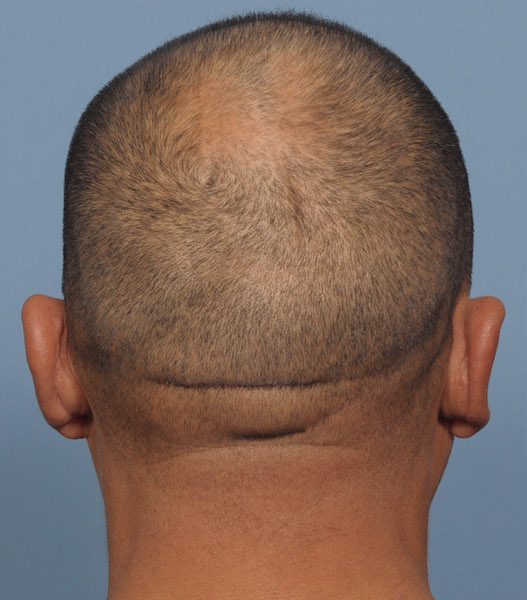

Patient 100

Desire for reshaping of an asymmetric flat back of the head in a shaved head male.

A combined back of the head reshaping procedure was done with a custom skull implant, sagittal ridge reduction and a right temporal muscle reduction.